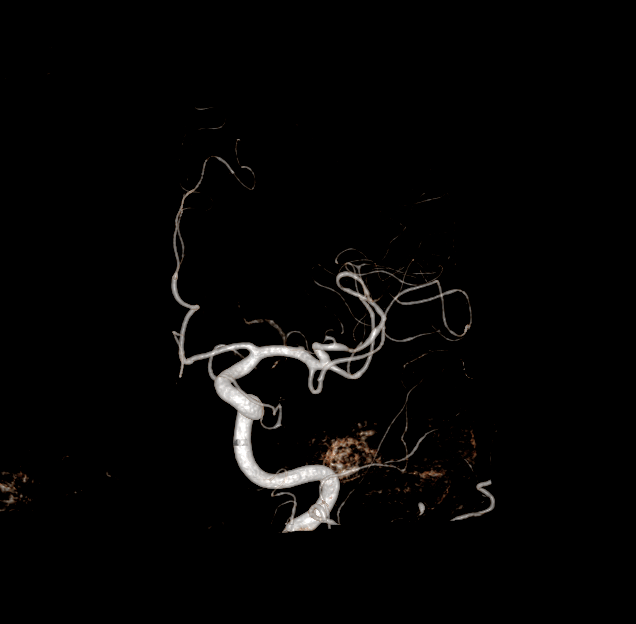

Malformations artério-veineuses (MAV)

Figure 1. MAV avant chirurgie